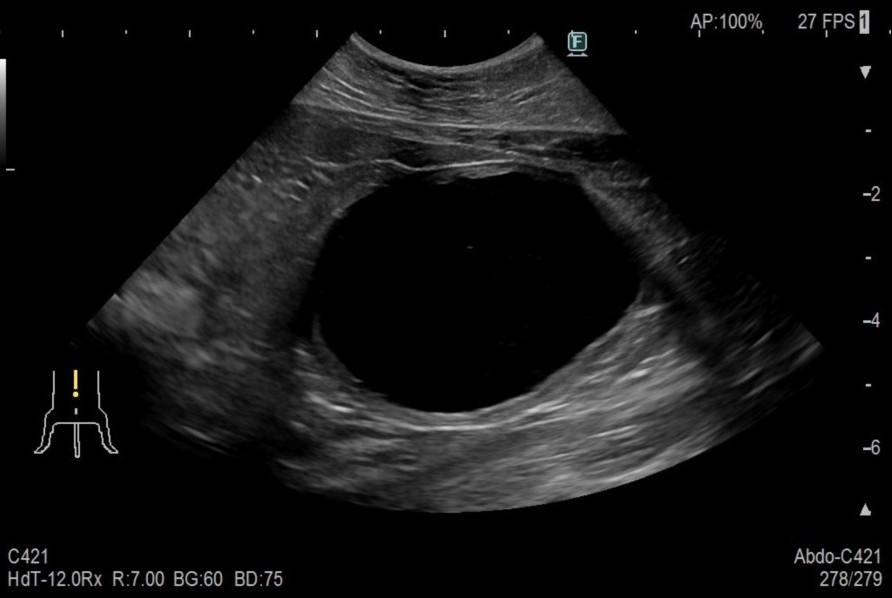

術後、スムーズに排尿できるようになり、術創の経過も良好であったため1週間程度で退院、術後2週間で抜糸を行い経過観察とした

after